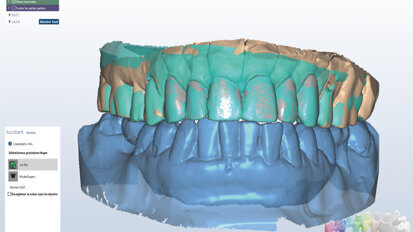

Nový úsměv za jeden den

Čt. 28. května 2020